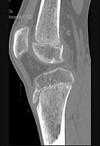

问题 男,46岁,膝关节疼痛,结合图像,最可能的诊断是()

选项 A.骨质硬化 B.骨质疏松 C.骨质软化 D.骨髓瘤 E.转移瘤

答案 B